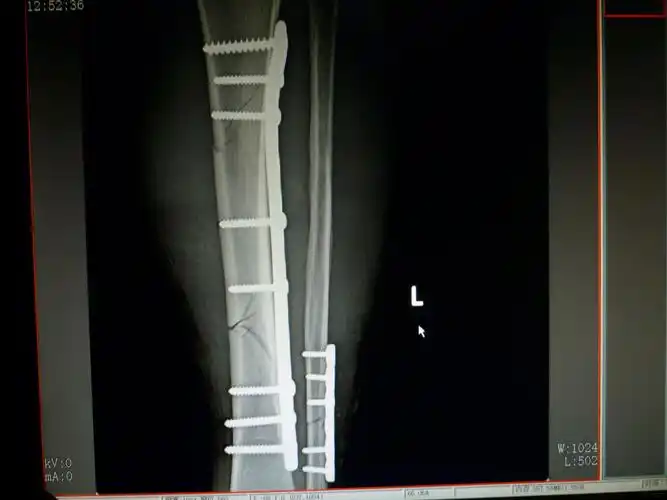

胫骨用髓内钉固定,腓骨用钢板胫骨骨折常规取钢板1_副本

胫骨骨折钢板内固定治疗一例